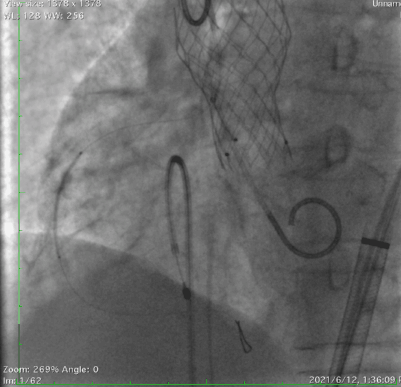

采用右冠guidezilla+预置支架保护,在右足Double-S体位下,选择Venus-A Valve 23瓣膜精准释放,跨瓣后及释放过程中患者持续低血压,释放2/3后血压仍无法恢复,调整好JR指引导管和guidezilla深度后,完全释放瓣膜。交换猪尾导管后复苏推药,患者血压逐渐恢复正常水平。

瓣膜释放后造影显示瓣膜定位准确,整个支架往右冠脉窦偏移,左冠显影正常,无遮挡。小心回撤guidezilla至冠脉口,JR指引导管内造影显示右冠脉遮挡仅留一条细线,决定植入烟囱支架,并充分后扩张。